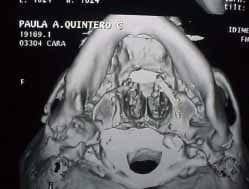

La reconstrucción exitosa, fue determinada mediante los criterios clínicos y radiográficos propuestos por Marx 16 y por August y Kaban (Figuras 6 al 9).(1)

![]() Fig. 6 |

![]() Fig. 7 |

![]() Fig. 8 |

![]() Fig. 9 |

Mediante estos criterios se estableció que 14 pacientes presentaron un procedimiento reconstructivo exitoso (82.35%), 2 (11.76%) fracaso y 1 (5.88%) no determinado (Tabla No. 1)